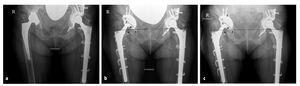

El cótilo utilizado en este trabajo es el AllofitSTM, que consiste en un componente acetabular pressfit de Protasul-Titan que se caracteriza por una pared de sólo 3 mm. Mediante un aumento a nivel ecuatorial de 2 mm y una disminución del diámetro a nivel polar de un mm, se obtiene el principio de pressfit según Morscher14,15 (fig. 1).

Figura 1. Cótilo AllofitSTM con exposición del aplanamiento polar y del pressfit ecuatorial de 2 mm.

La superficie del cótilo dispone de unos 1.200 punchones en disposición radial de 1 mm que aumentan la superficie de contacto hasta un 80%. En el borde del cótilo se hallan hasta seis anclajes para asegurar la estabilidad rotacional en el hueso. Estos anclajes salen perpendiculares y se reparten hacia la periferia (fig. 1), lo cual facilita un mejor asentamiento al colocar el implante. Con cada golpe el cótilo progresivamente se ancla más hasta el pressfit necesario. Nosotros utilizamos el implante AllofitSTM en cirugía de revisión con un pressfit de 4 mm, con lo cual elegimos el implante de una talla superior a la última fresa.